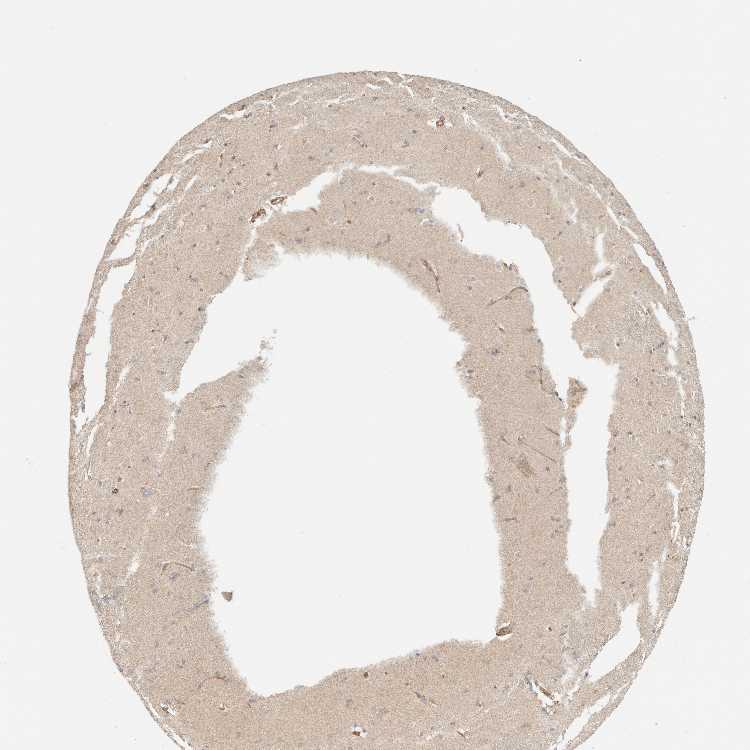

CAUDATE - Antibody stainingi

Antibody staining in the annotated cell types in the current human tissue is reported as not detected, low, medium, or high, based on conventional immunohistochemistry profiling in selected tissues. This score is based on the combination of the staining intensity and fraction of stained cells.

Each image is clickable and will lead to virtual microscopy that enables deeper exploration of all samples and also displays staining intensity scores, fraction scores and subcellular localization as well as patient and tissue information for each sample.

Antibody HPA001869Antibody HPA023882

Glial cells HighNot detected

Neuronal cells HighLow